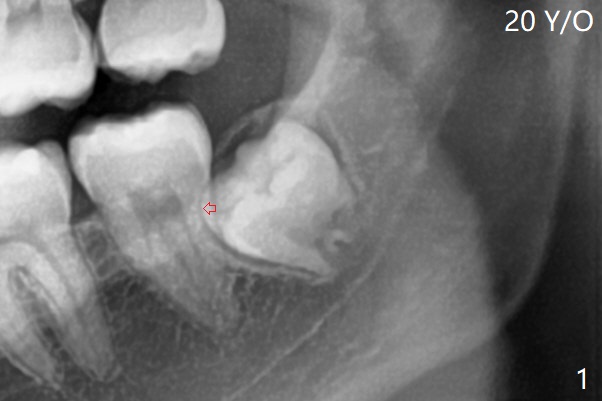

After extraction, one piece of Osteogen Plug is placed; the anterior end of the Internal Oblique Ridge (Fig.2 I) is located in the posterior of the socket.  As the socket heals, the anterior end of the ridge is expected to advance.